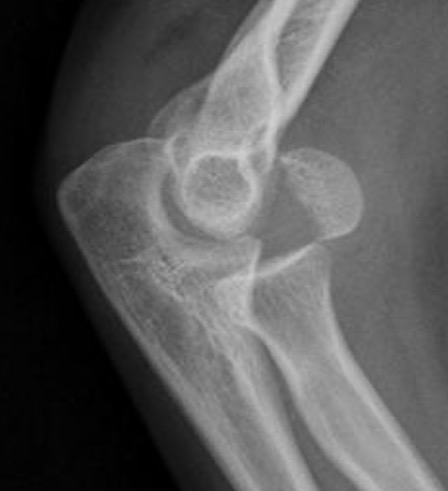

Knee

ApproachesPosterior approach knee